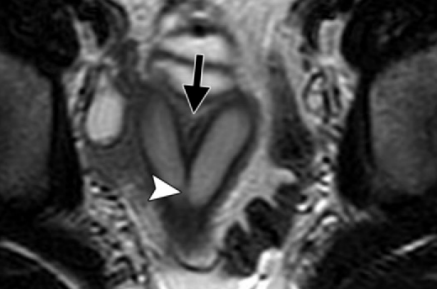

Uterus Septé

Bicorne VS Septé